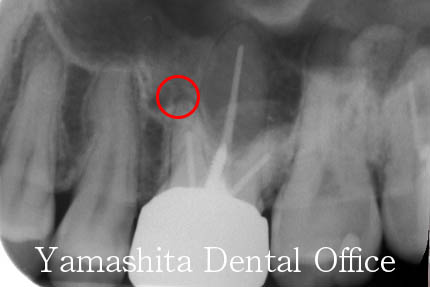

神経を取る治療を行った直後、治療が終わったはずなのにかむと違和感がするとのことで来院されました。レントゲン上で、根管形成の不足と赤丸の部分に骨の中に病巣と思われる像が確認されました。

ラバーダムとマイクロスコープを使用した精密根管治療により、症状は改善しました。根管充填後のレントゲン写真です。